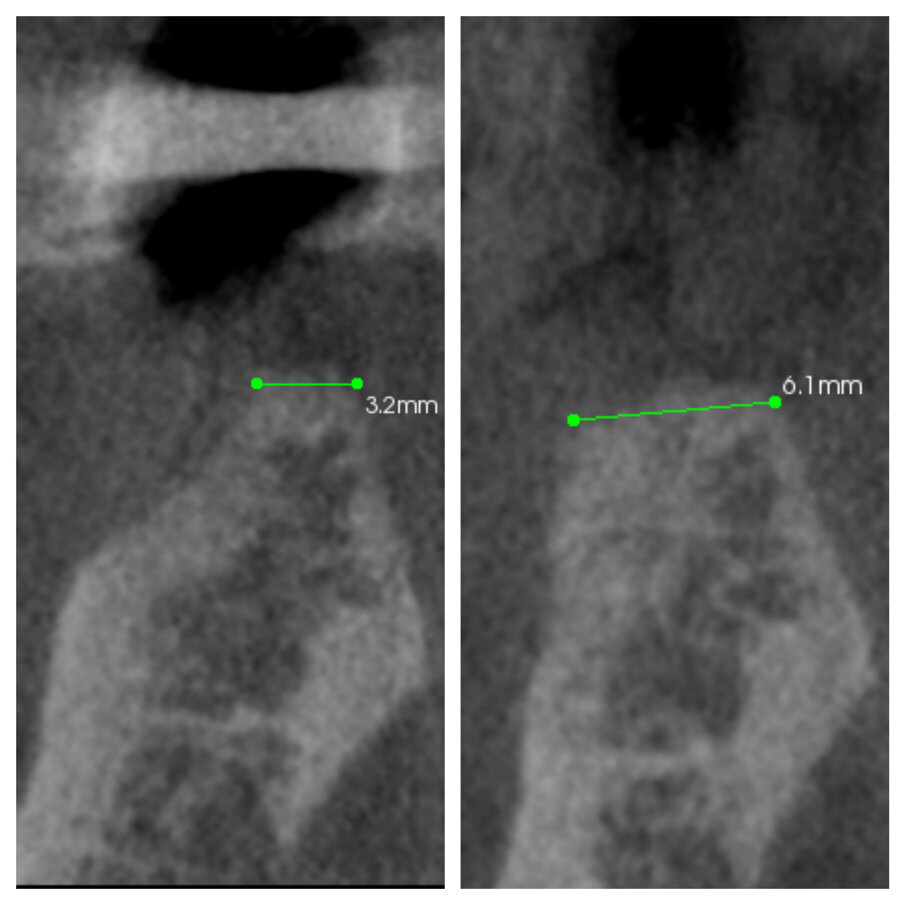

Fig. 1c_Aumento orizzontale dei tessuti duri del 50%.

Fig. 2c_CBCT pre e post intervento a 6 mesi.

Fig. 3c_CBCT pre intervento e dopo 6 mesi a confronto.